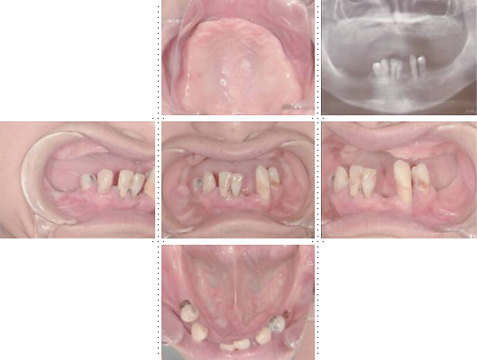

症例2

62才 女性

上顎は総義歯、下顎はブリッジと局部床義歯が装着。義歯は違和感があり、食事も不便を感じ、審美的にも人前にでるのが苦痛に感じていました。この状態を打破するためにも、「インプラント治療に自分の人生を賭けてみたい」という覚悟で来院されました。インプラント手術に対する恐怖心も強くお持ちでした。このような骨幅が狭いケースでは、X線撮影と共にCT撮影による画像診断とインプラント埋入シミュレーションが重要です。

下顎は両側犬歯を残し、他は抜歯。インプラント7本埋入。 上顎はインプラント8本埋入。 インプラント手術を受けられる患者さんは、前の晩眠れない程の不安感、恐怖心を持って来院されます。実際には麻酔注射は痛みを感じず、インプラント手術も痛みも無く、短時間(1本平均3分)で終わるという、当院独自のテクニックにより、2回目からのインプラント手術は気楽になるようです。 前歯は仮歯の段階で患者さん、歯科医、技工士の三者で、審美性・機能性の面から10回以上形態修正を繰り返し検討した後、上・下顎共に前歯・小臼歯はセラミック(MB)クラウン、大臼歯はゴールドクラウンを装着。ご本人とご家族の方にも、「アンチエイジングには、審美インプラント治療が一番効果あり」と大変喜んで頂きました。